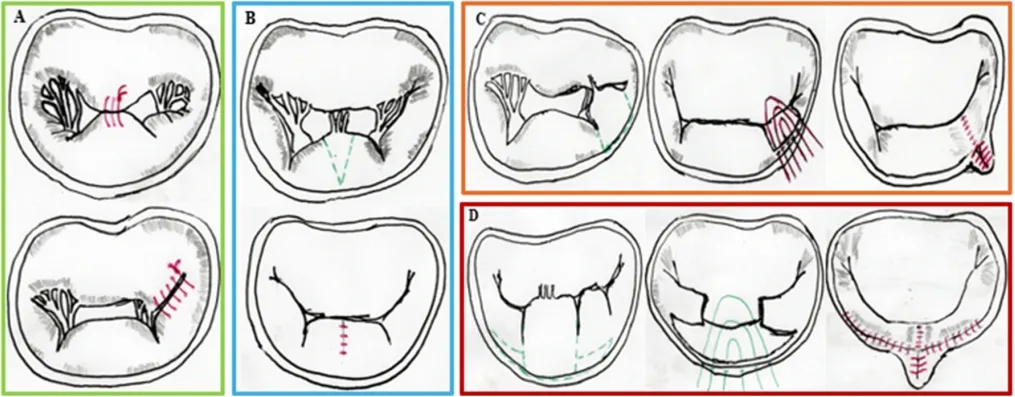

在腱索置换领域,NeoChord DS1000系统和HARPOON TSD-5系统提供经心尖、心脏不停跳入路至二尖瓣,能够为孤立瓣叶脱垂患者靶向植入人工腱索。这些系统在具有良好解剖结构的选定患者中,在手术成功率、瓣叶稳定和持久减少二尖瓣反流方面显示出良好的结果。尽管这些系统仍未得到充分利用,在经验丰富的医疗中心外应用有限,但它们体现了经导管二尖瓣修复术日益增长的多功能性。然而,从技术角度来看,与经导管方法相比,外科手术方法允许进行更复杂和多样化的人工腱索植入,而经导管方法的手术受到入路部位和装置性能的限制(图3)。

图3.不同外科腱索植入技术的示意图:从左上角开始顺时针方向,展示了以下外科技术:罗马拱技术、米诺陶技术、“V”形技术、方形技术、ARGO技术和束带技术;缝线以绿色表示;在某些情况下,绘制了虚线以更好地描绘缝线的路径。